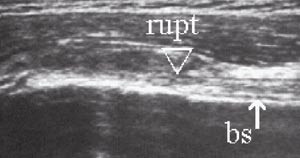

Rotatorcuffrupturer klassifiseres med ultralyd ut fra lokalisasjon, størrelse og grad (partiell, full tykkelse). Hovedlokalisasjonen er distalt i supraspinatussenen ved festet mot tuberculum majus (1). Det er beskrevet tre hoved- og tre tilleggskriterier for ultralydfunn ved cuffrupturer (3, 5). Hovedkriteriene har størst betydning og det kreves påvisning av minst ett av hovedkriteriene i to plan for ultralyddiagnosen rotatorcuffruptur. Sammen med et hovedkriterium støtter hvert av tilleggskriteriene sannsynligheten for diagnosen. Hovedkriteriene er hypoekkoisk defekt (fig 7), tap av konveksitet (fig 8 a, b) og skallet humerushode (fig 9a, b). Hypoekkoisk defekt er typisk for akutte rupturer og representerer en væskeansamling i defekten mellom rupturkantene (1). Tap av konveksitet og skallet humerushode er stadier i en progredierende degenerativ prosess med gradvis skade og retraksjon av rupturendene og herniering av bursavev og deltoidmuskel i defekten.

De tre tilleggskriteriene er den markerte fremstillingen av brusklaget i bunnen av cuffdefekten (double cortex sign) (fig 7), overflateforandringer på tuberculum majus (fig 8b) og væskeansamling i leddet og/eller bursa (fig 10a, b). Forandringene på tuberculum majus er følge av en mikrotraumatisering mellom den nakne beinoverflaten og acromion. Væskeansamling i leddet er best synlig i seneskjeden rundt det lange bicepshodet som hypoekkoisk halo, eller ved utposning av bakre leddkapsel (2, 6). Hollister og medarbeidere (7) fant en positiv prediktiv verdi for rotatorcuffruptur på 60 % ved væske i leddet, 70 % ved væske i bursa og 95 % ved væske begge steder, verifisert ved operasjon.

Bicepsseneruptur finnes isolert eller i forbindelse med rotatorcuffruptur. Kriteriene for ruptur er avbrekk av den fibrillære senestrukturen i lengdesnitt (e-fig 13) og manglende senefremstilling i sulcus intertubercularis i tverrsnitt (1, 3).